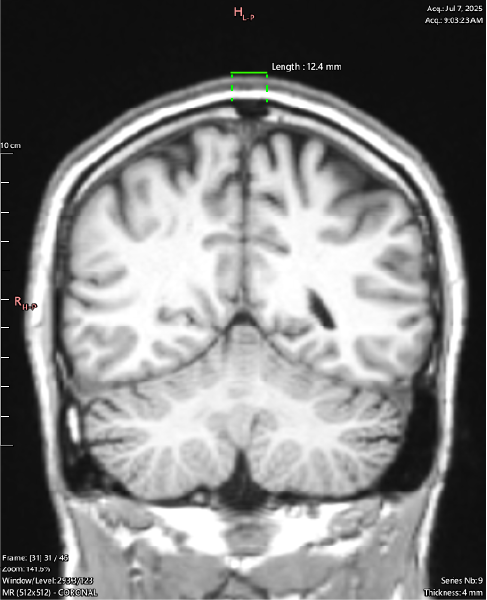

<- (Length 12.4mm)

T1 Coronal

Coronal view shows this is happening along the Sagittal Suture - cranial sutures should return a uniform signal void (black) across all sequences as they are dense structures with little to no free water movement.

It can be seen throughout the JULY 2025 MRI series that a majority of the cranial sutures are instead filled with variable hypointense signaling describing dense, fibrous tissue.

By the age of 33 the cranial sutures should be almost - if not entirely - fused, showing as a thin (approx. 2mm) black zig-zag along their respective paths, if showing at all.

My Sagittal Suture in these images shows as 12.4mm wide at the outside margin, clearly showing atypical imaging presentation, indicating an underlying process occurring.

^ (Length 12.4mm) ^